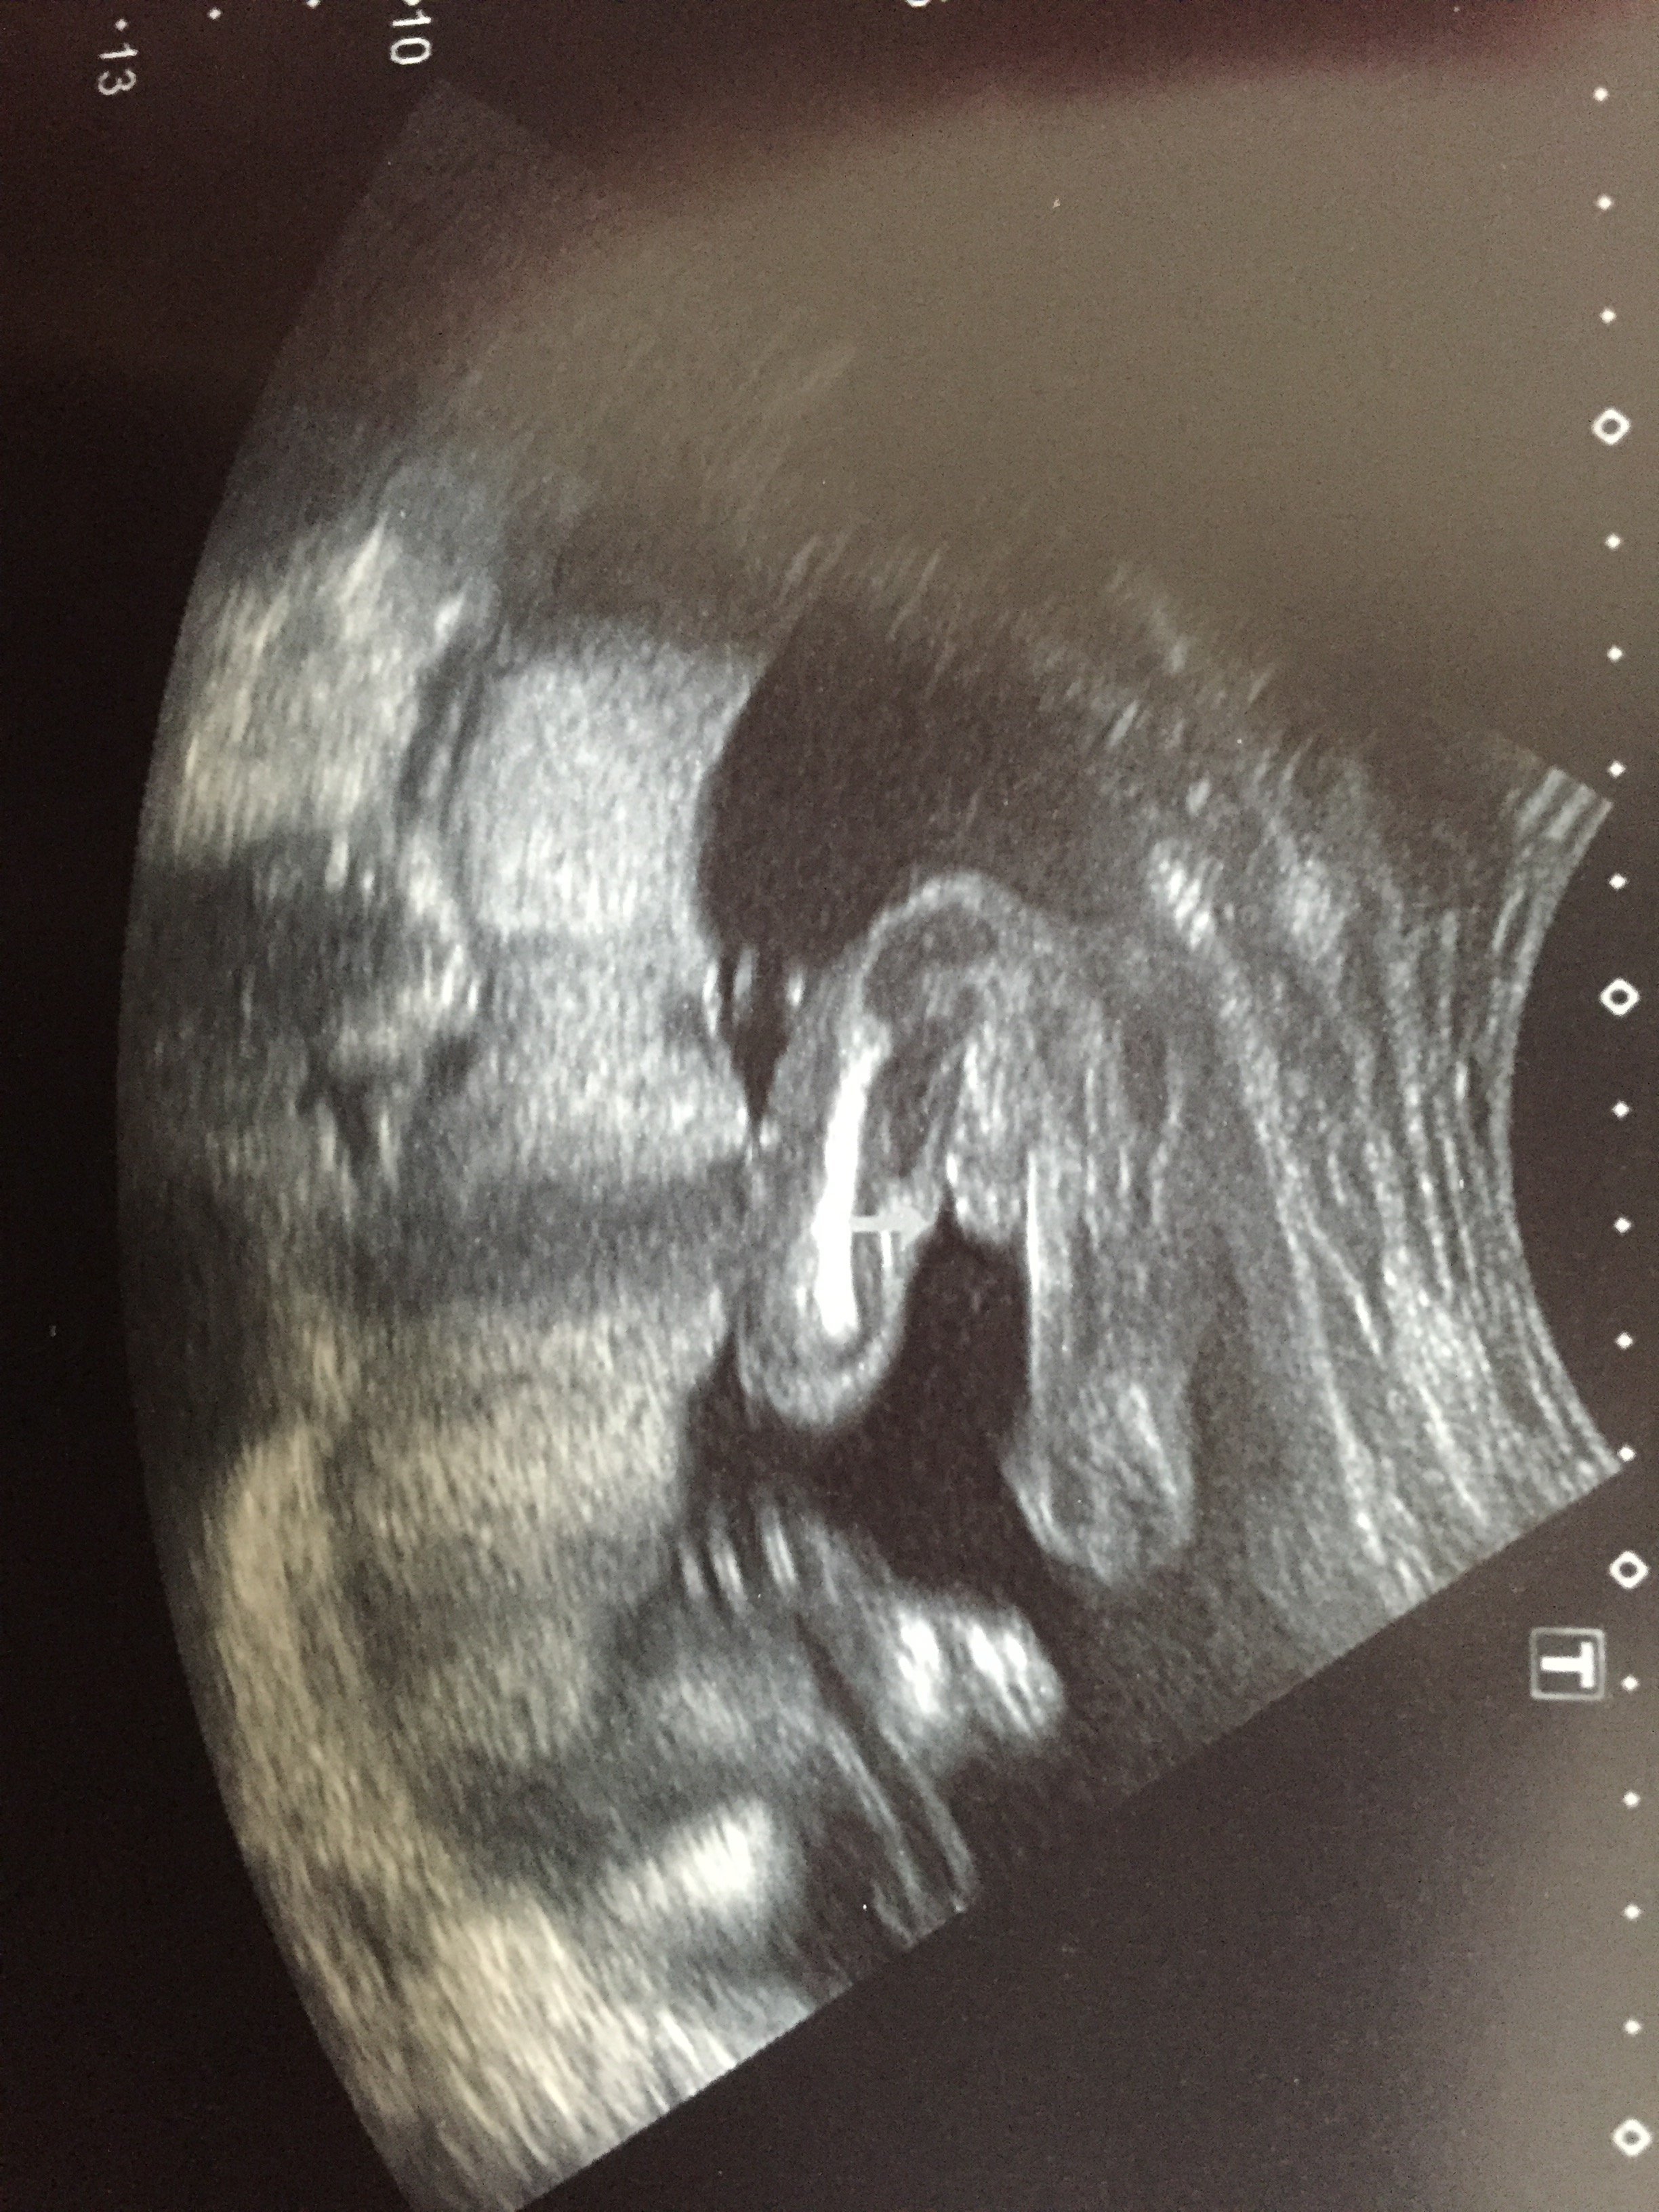

20週1日の時のエコーです。男の子って言われたのですが、まだ確定じゃ